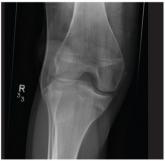

A 20-year-old man presents following a motor vehicle collision in which the car he was driving was broadsided by another vehicle. His air bag deployed...